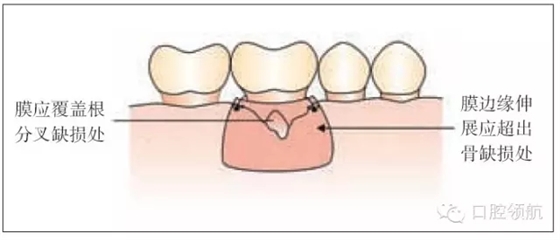

圖26.3 引導(dǎo)組織再生術(shù):膜的放置

·修剪膜使它大小既能覆蓋缺損同時(shí)輕輕延伸超過(guò)它的邊緣(圖26.3)。